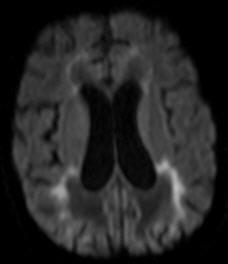

• Confluent, symmetric deep WM w/ Confluent, symmetric deep WM w/ leading edge enhancement leading edge enhancement

• Posterior in 80% Posterior in 80%

• Pons and medulla Pons and medulla